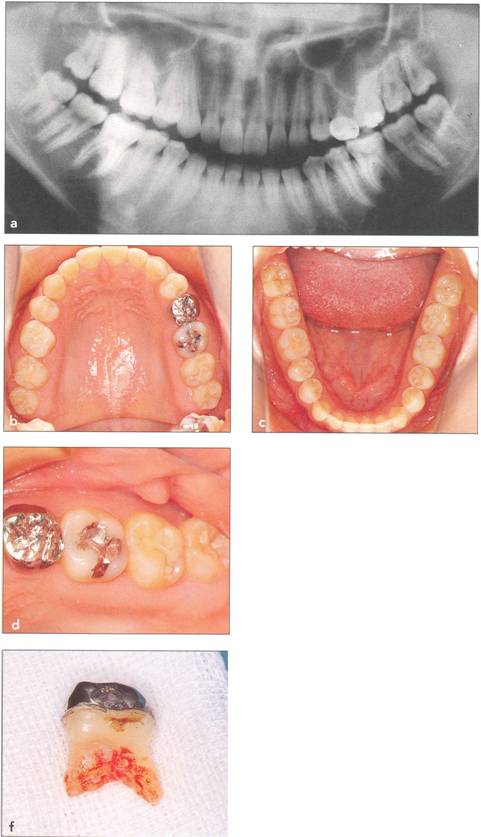

Fi 545e45f g 5-1a Preoperative panoramic view. The patient is a 24-year-old female. Transplantation of the mandibular right third molar to the area of nonrestorable mandibular first molar is planned. |

Fi 545e45f gs 5-1b and 5-1c Maxillary and mandibular teeth after initial periodontal treatment of brushing, scaling, and root planing. |

Fi 545e45f g 5-1d Preoperative periapical radiograph. |

Fi 545e45f g 5-1e Preoperative view of the donor tooth and the recipient site. |

Fi 545e45f g 5-2a Panoramic view on first visit of a nineteen-year-old female patient. The maxillary right third molar will be transplanted to the area of the nonrestorable mandibular right first molar. |

Fi 545e45f gs 5-2b and 5-2c Preoperative view of the maxillary and mandibular arches. |

Fi 545e45f g S.3a Panoramic view at the first visit. Maxillary left third molar will be transplanted to the area of nonrestorable mandibular left second molar in a 21-year-old male. |

Fi 545e45f g 5-4a Pretreatment panoramic view. Mandibular left third molar will be transplanted to the area of the non restorable mandibular left second molar in a 39-yearold male. |

Fi 545e45f gs 5-4b and 5-4c Preoperative view. |

Fi 545e45f gs 5-4d and 5-4e Preoperative view of the recipient site and the donor tooth. |

Fi 545e45f g 5-4f Extracted second molar, which will be discarded. Fi 545e45f g Extracted donor tooth. The amount of periodontalligament is adequate. Transplantation was performed 6 weeks after extraction of the tooth from the recipient site. Fi 545e45f g 5-4h View of the donor site and preparation of the recipient site. |

Fi 545e45f g 5-4i After the gingival flap has been sutured and the donor tooth has been splinted. The distal aspect of the donor tooth is closed as tightly as possible. Fi 545e45f g 5-4j After transplantation. Fi 545e45f g 5-4k Two weeks after trans plantation |

Fi 545e45f g 5-41 Six weeks after transplantation. The root canals have been cleaned, shaped, and filled with calcium hydroxide. Fi 545e45f g 5-4m Three months after transplantation. The radiograph was taken after removing the splint. Fi 545e45f g 5-4n Seven months after transplantation. |

Fi 545e45f g 5-40 Seven months after transplantation. Mesial migration of the donor tooth and regeneration of alveolar bone can be observed. Fi 545e45f g 5-4p One year after transplantation. Fi 545e45f g 5-4q Two years after transplantation. |

Fi 545e45f gs 5-4r to 5-4t One year 6 months after transplantation. The donor tooth is restored with composite resin. |

Fi 545e45f g 5-4u Three years after transplantation. |